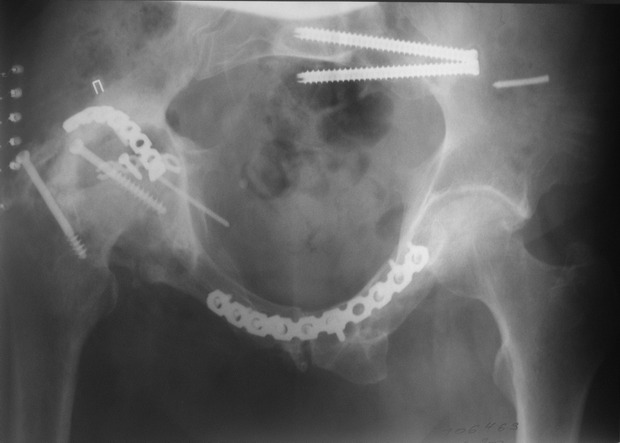

Пациент 49 лет, паровозная травма 23.2.2006, получил вертикальная

нестабильное повреждение таза, разрыв левого крестцово-подвздошного

сочленения, перелом лонной, седалищной костей слева, T-образный

оскольчатый перелом правой вертлужной впадины с переломом заднего

края, вывих правого бедра, посттравматическая пояснично-крестцовая

плексопатия с обеих сторон, паралич мышц правой голени.

В день травмы - вправление вывиха, скелетное вытяжение, 14.3.2006

чрескостный остеосинтез таза. 20.4.2006 остеосинтез правой вертлужной

впадины пластинами, осложнившийся нагноением межмышечной гематомы

правой ягодичной области. Получал консервативное лечение, было

достигнуто полное заживление раны. 24.7.2006 введены илиосакральные

винты слева. С декабря 2006 года и по настоящее время ходит на

костылях без опоры на правую ногу. Планируется THA. Помогите

определиться с вариантом костной пластики? И какую укрепляющую

конструкцию использовать?